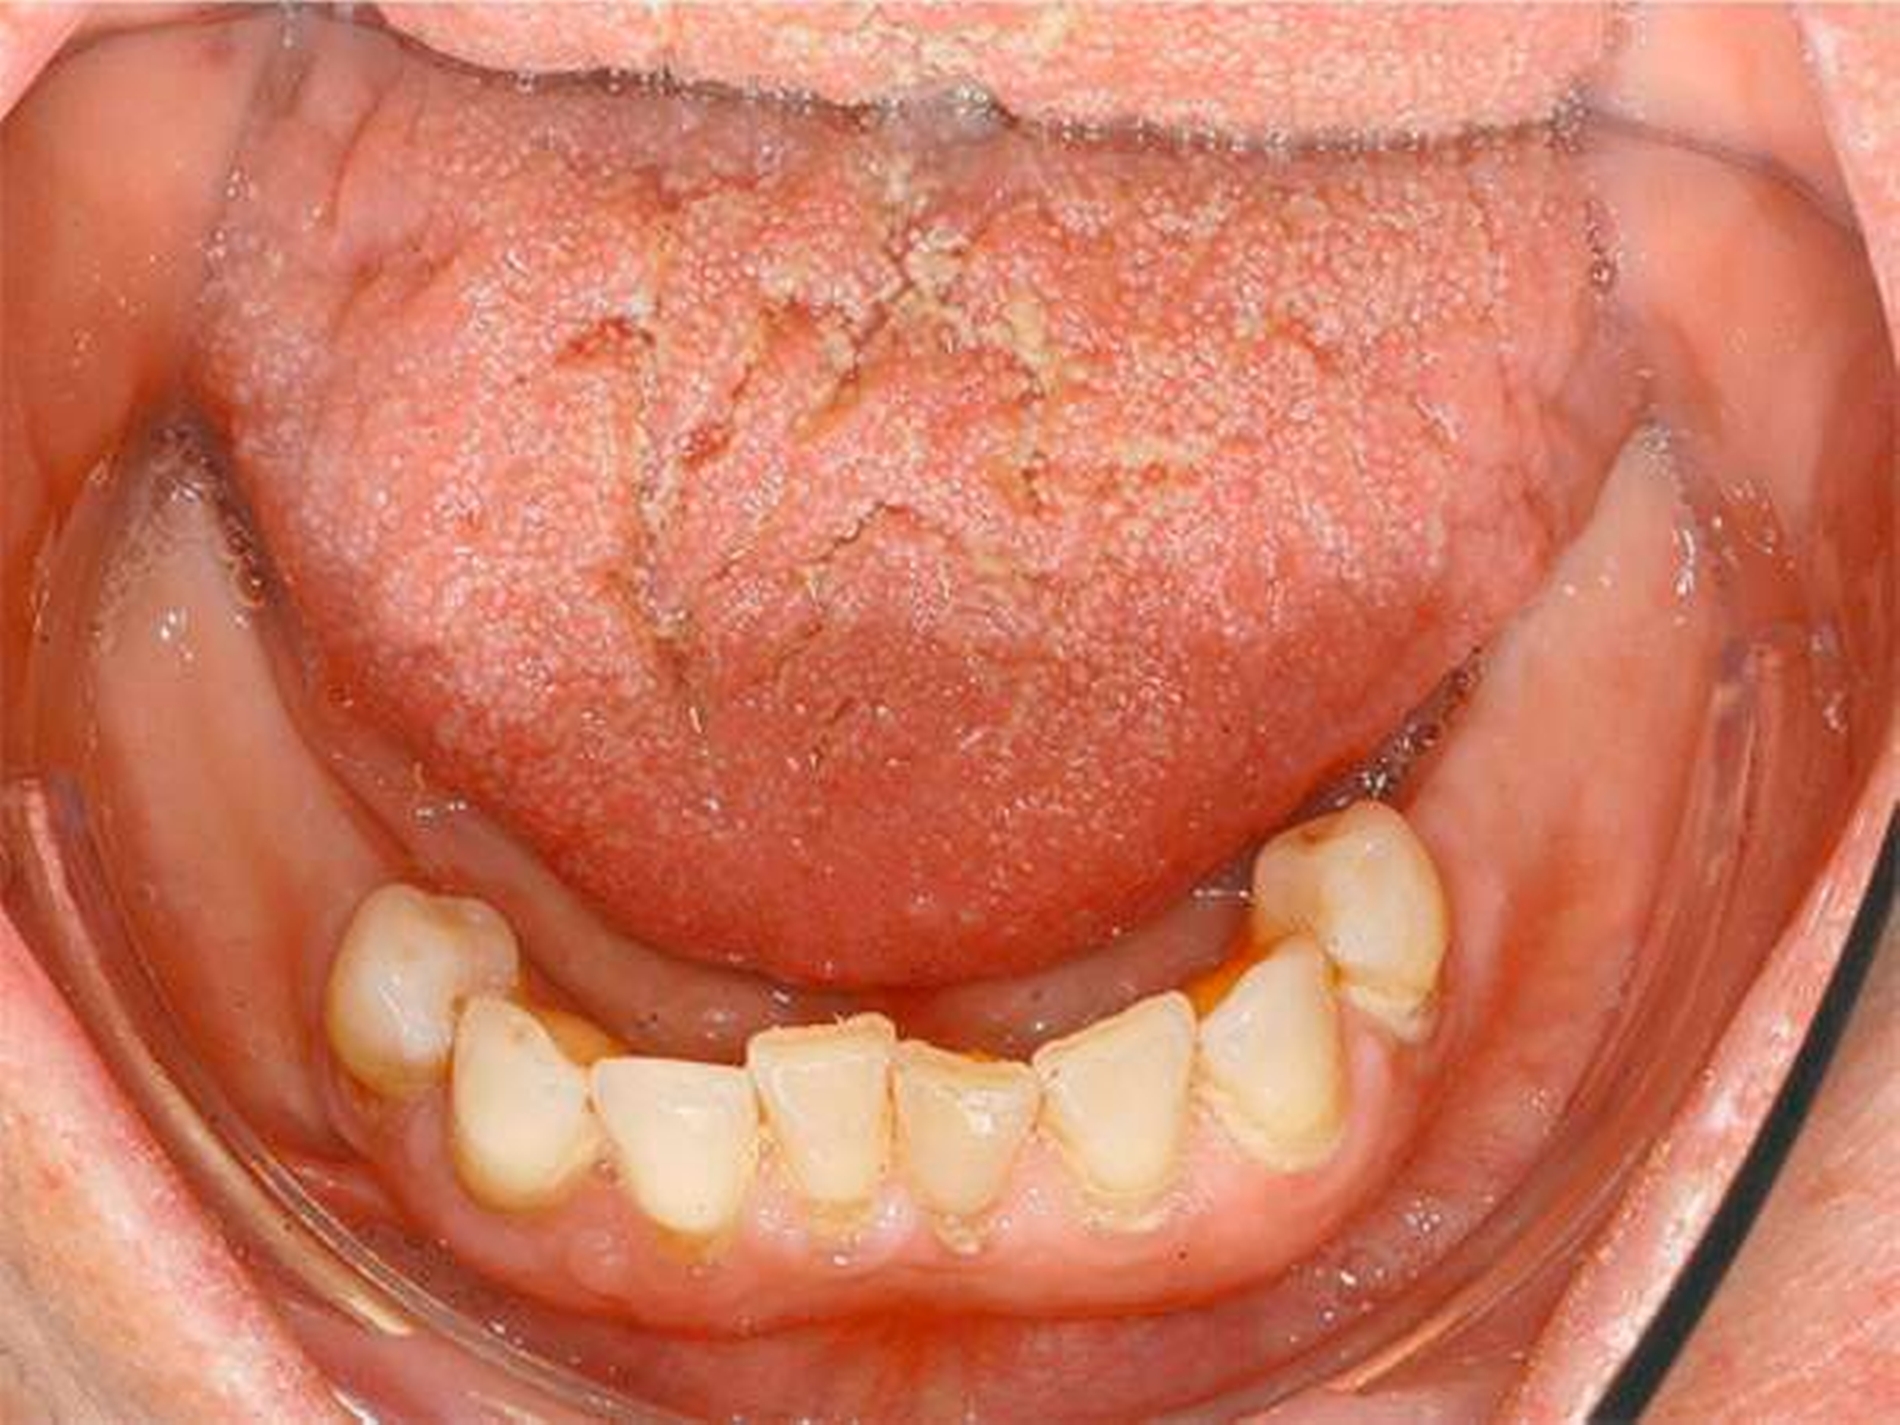

Eine Woche nach Abschluss der internistischen Therapie stellte sich die Patientin zur Verlaufskontrolle in unserer Klinik vor, dabei zeigte sich eine vollständige Remission der hyperplastischen Gingiva bei weiterhin insuffizienter Mundhygiene (Abbildungen 4 und 5).